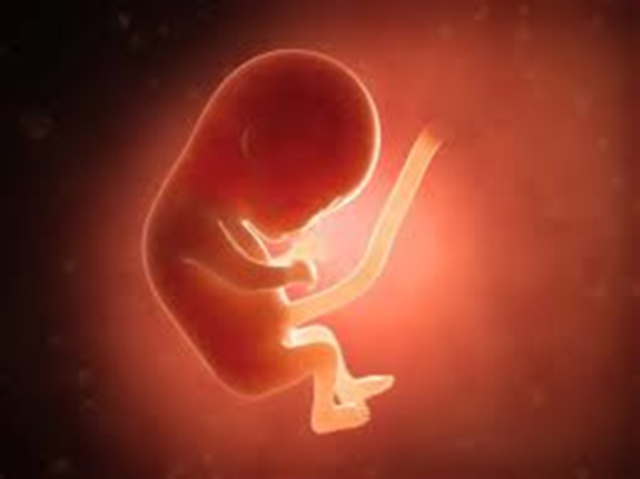

• 3 er mes 9.a - 10. a semanas

3 er mes 9.a - 10. a semanas

El hígado casi esta desarrollado totalmente; aparecen los riñones definitivos y el feto empieza a verter orina en el líquido amniótico. La cara casi constituido, progresivamente, adquiere una forma más «humana»:. Los ojos, que estaban muy separados y situados a cada lado de la cabeza, están ahora de frente, recubiertos por los párpados; se dibujan los labios; y las orejas son como dos pequeñas ranuras. Los miembros se alargan, en especial los brazos.